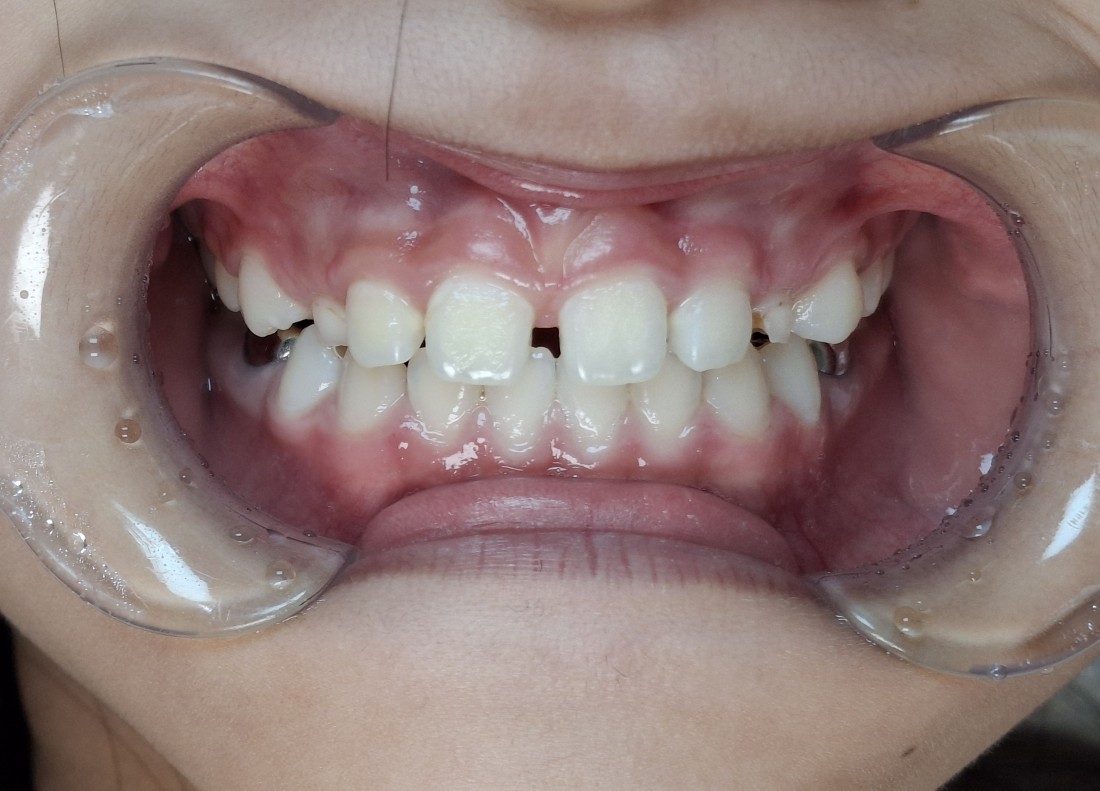

프리올소 교정장치는

현재 서울대학교 소아치과 교정과,

연세대학교 소아치과 교정과에서

교수님들이 정말 많은 빈도로 처방하고 있는

소아부정교합 개선 방법입니다.

광주 부정교합 치과 중에서는

서울우리아이치과에서

광주/전남 프리올소 사용량 1위 치과로

굉장히 많은 케이스를 다루고 있으며,

성공적인 소아부정교합 개선 사례를

많이 공유해드리고 있습니다.